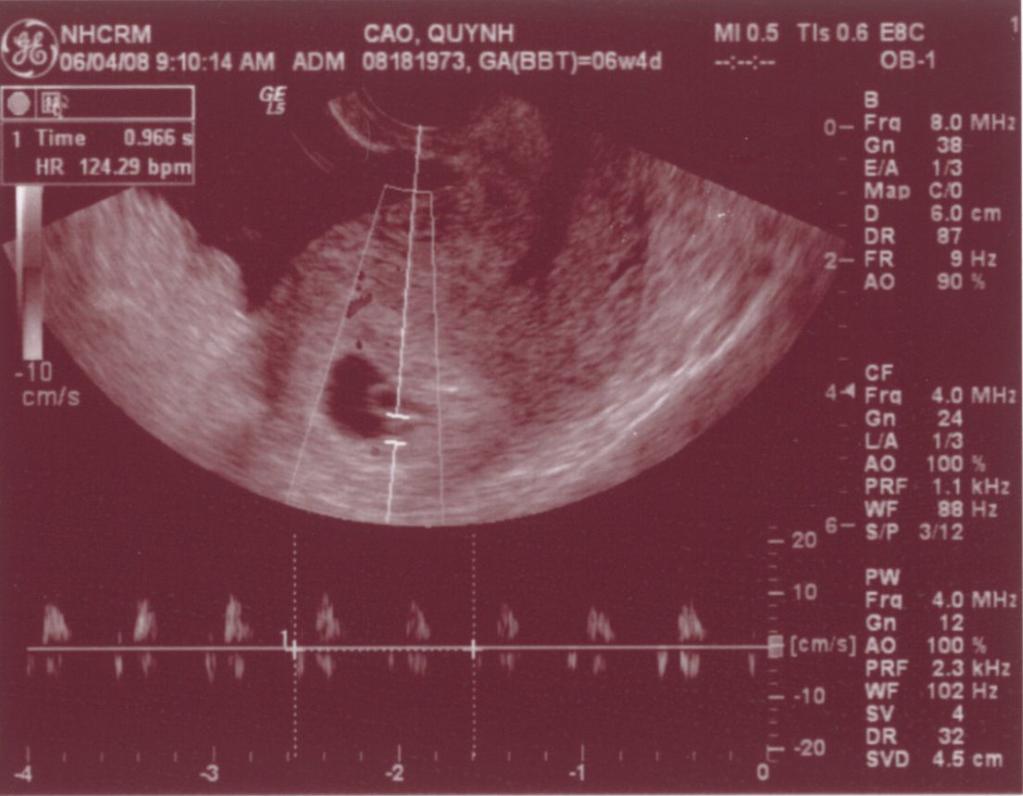

Ngày 11/28/1999 Ba Mẹ có nhau, lúc đó con ở đâu ha? Ngày 5/27/2008, con đây rồi!!! Mới được 2 tuần, là hạt nhân nhỏ xíu trong bụng Mẹ thôi Ngày 6/4/08, lần đầu tiên Ba Mẹ nghe tim con đập, 124 nhịp/phút. Mẹ sung sướng nhìn con. Còn Ba thì rơm rớm nước mắt, hihi!! Ngày 7/8/2008, con được 11 tuần rồi, bắt đầu có tay chân rồi đây... 1 tuần sau tay chân con đã dài ra rồi, lẹ ghê... ...biết nhào lộn vòng vòng nữa, mới nằm úp giờ nằm ngửa rồi. Ngày 9/3/2008, Mẹ chưa muốn biết con là trai hay gái vì muốn bất ngờ, nhưng rồi cuối cùng cũng không đợi được... ...hihi, cục cưng của Ba Mẹ là con trai. Con trai miệng bự giống Ba.  19 tuần là mắt mũi miệng đầy đủ hén. Từ khi biết có con, Mẹ nhờ Ba chụp hình hai mẹ con mình. Cái này là lúc con được 2 tháng trong bụng Mẹ.. ...24 tuần, con bắt đầu cựa quậy lung tung mỗi ngày... ...36 tuần, có lúc Ba Mẹ tưởng đã mất con nhưng con vẫn lớn giỏi ngoan... ..39 tuần, con nặng quá rồi nhưng Mẹ vẫn muốn con ở trong đó thêm chút nữa cho lớn lớn... Ba thì nôn gặp con quá, ngày nào Ba cũng nói chuyện với con.  Bụng Ba cũng bự rồi nè! Ngày 1/20/2009, con 39 tuần, bác sĩ muốn con ra sớm cho an toàn.  Ba Mẹ hồi hộp đợi tới lúc gặp con... Sau gần 8 tiếng chờ đợi thì con ra đời!! Con mở mắt nhìn Mẹ như là biết rồi đó.  Thương con ghê nơi! 1 tuần tuổi thì rụng rún.  2 tuần tuổi thì chụp hình lần đầu với Mẹ, nhỏ xíu xiu xiu... 7 tháng (8/2009) con bò lung tung, chụp hình mà không yên... 14 tháng (4/2010) con chỉ muốn chạy chơi thôi, Ba chụp lẹ lẹ nghe. Ngày 2/19/2010 Ba Mẹ làm lễ cưới ở nhà thờ.  Lần này thì có con rồi.  Có con Ba Mẹ có tất cả...